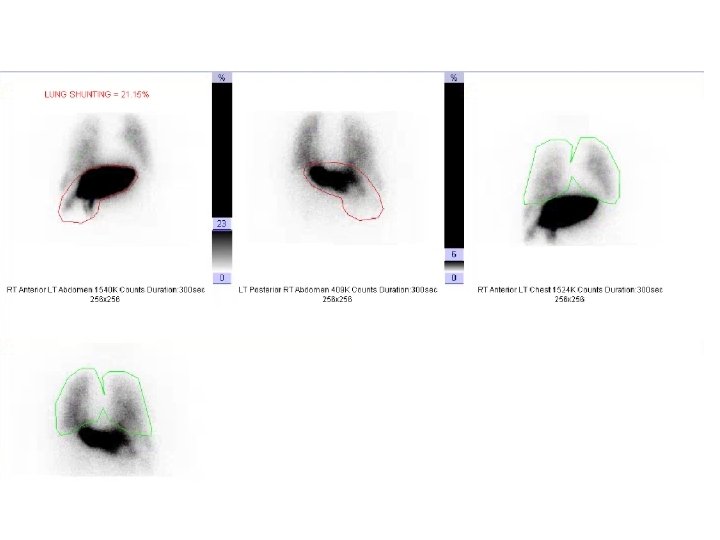

MAA Scan

Dose reduction for lung shunting • BSA method – Dosage (GBq) = [(BSA –

Dose reduction for lung shunting • BSA method – Dosage (GBq) = [(BSA – 0. 2) + (% tumor involvement/100)] * (%treatment area represents of whole liver/100) (1 -(%lung shunt reduction/100)) • Recommended lung shunt reduction – <10% = no reduction – 10% - 15% = 20% dosage reduction – 15% - 20% = 40% dosage reduction – >20% = no treatment • No reduction for lung shunting may be considered if the lung dose is less than 25 Gy per treatment and 50 Gy cumulative dose to the lung. • Lung dose (Gy) = (dosage in GBq * lung shunt fraction) * 50/ lung mass (Kg) Assume lung mass is 1 kg • A 25% dosage reduction may be considered when teating patients with a total bilirubin >2